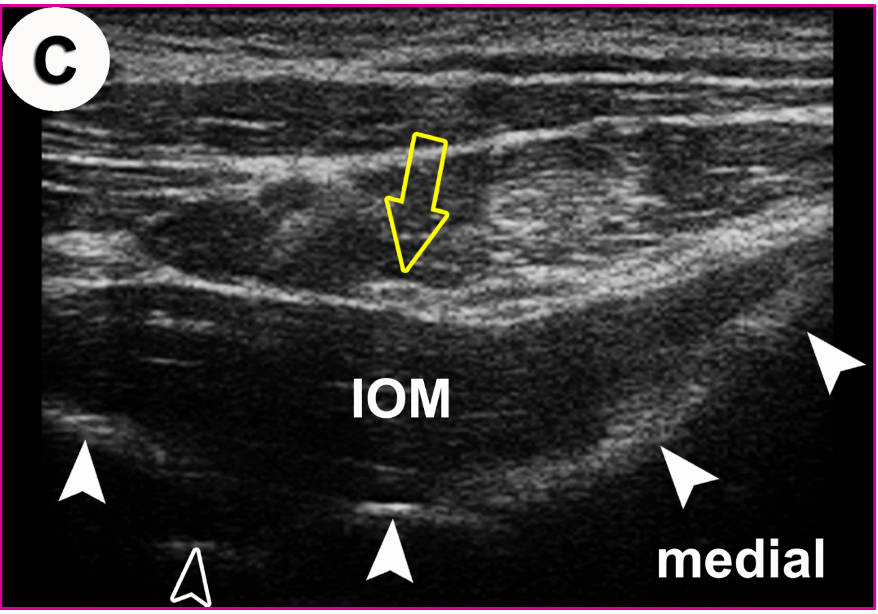

Korrespondierendes US-Bild mit Darstellung des N. occipitalis major (Pfeil) auf dem Kennmuskel (IOM). Gefüllte Pfeilköpfe: Konturen (Oberfächenreflex) des Axis und Atlas. Offener Pfeilkopf: weist auf die Lage der A. vertebralis.